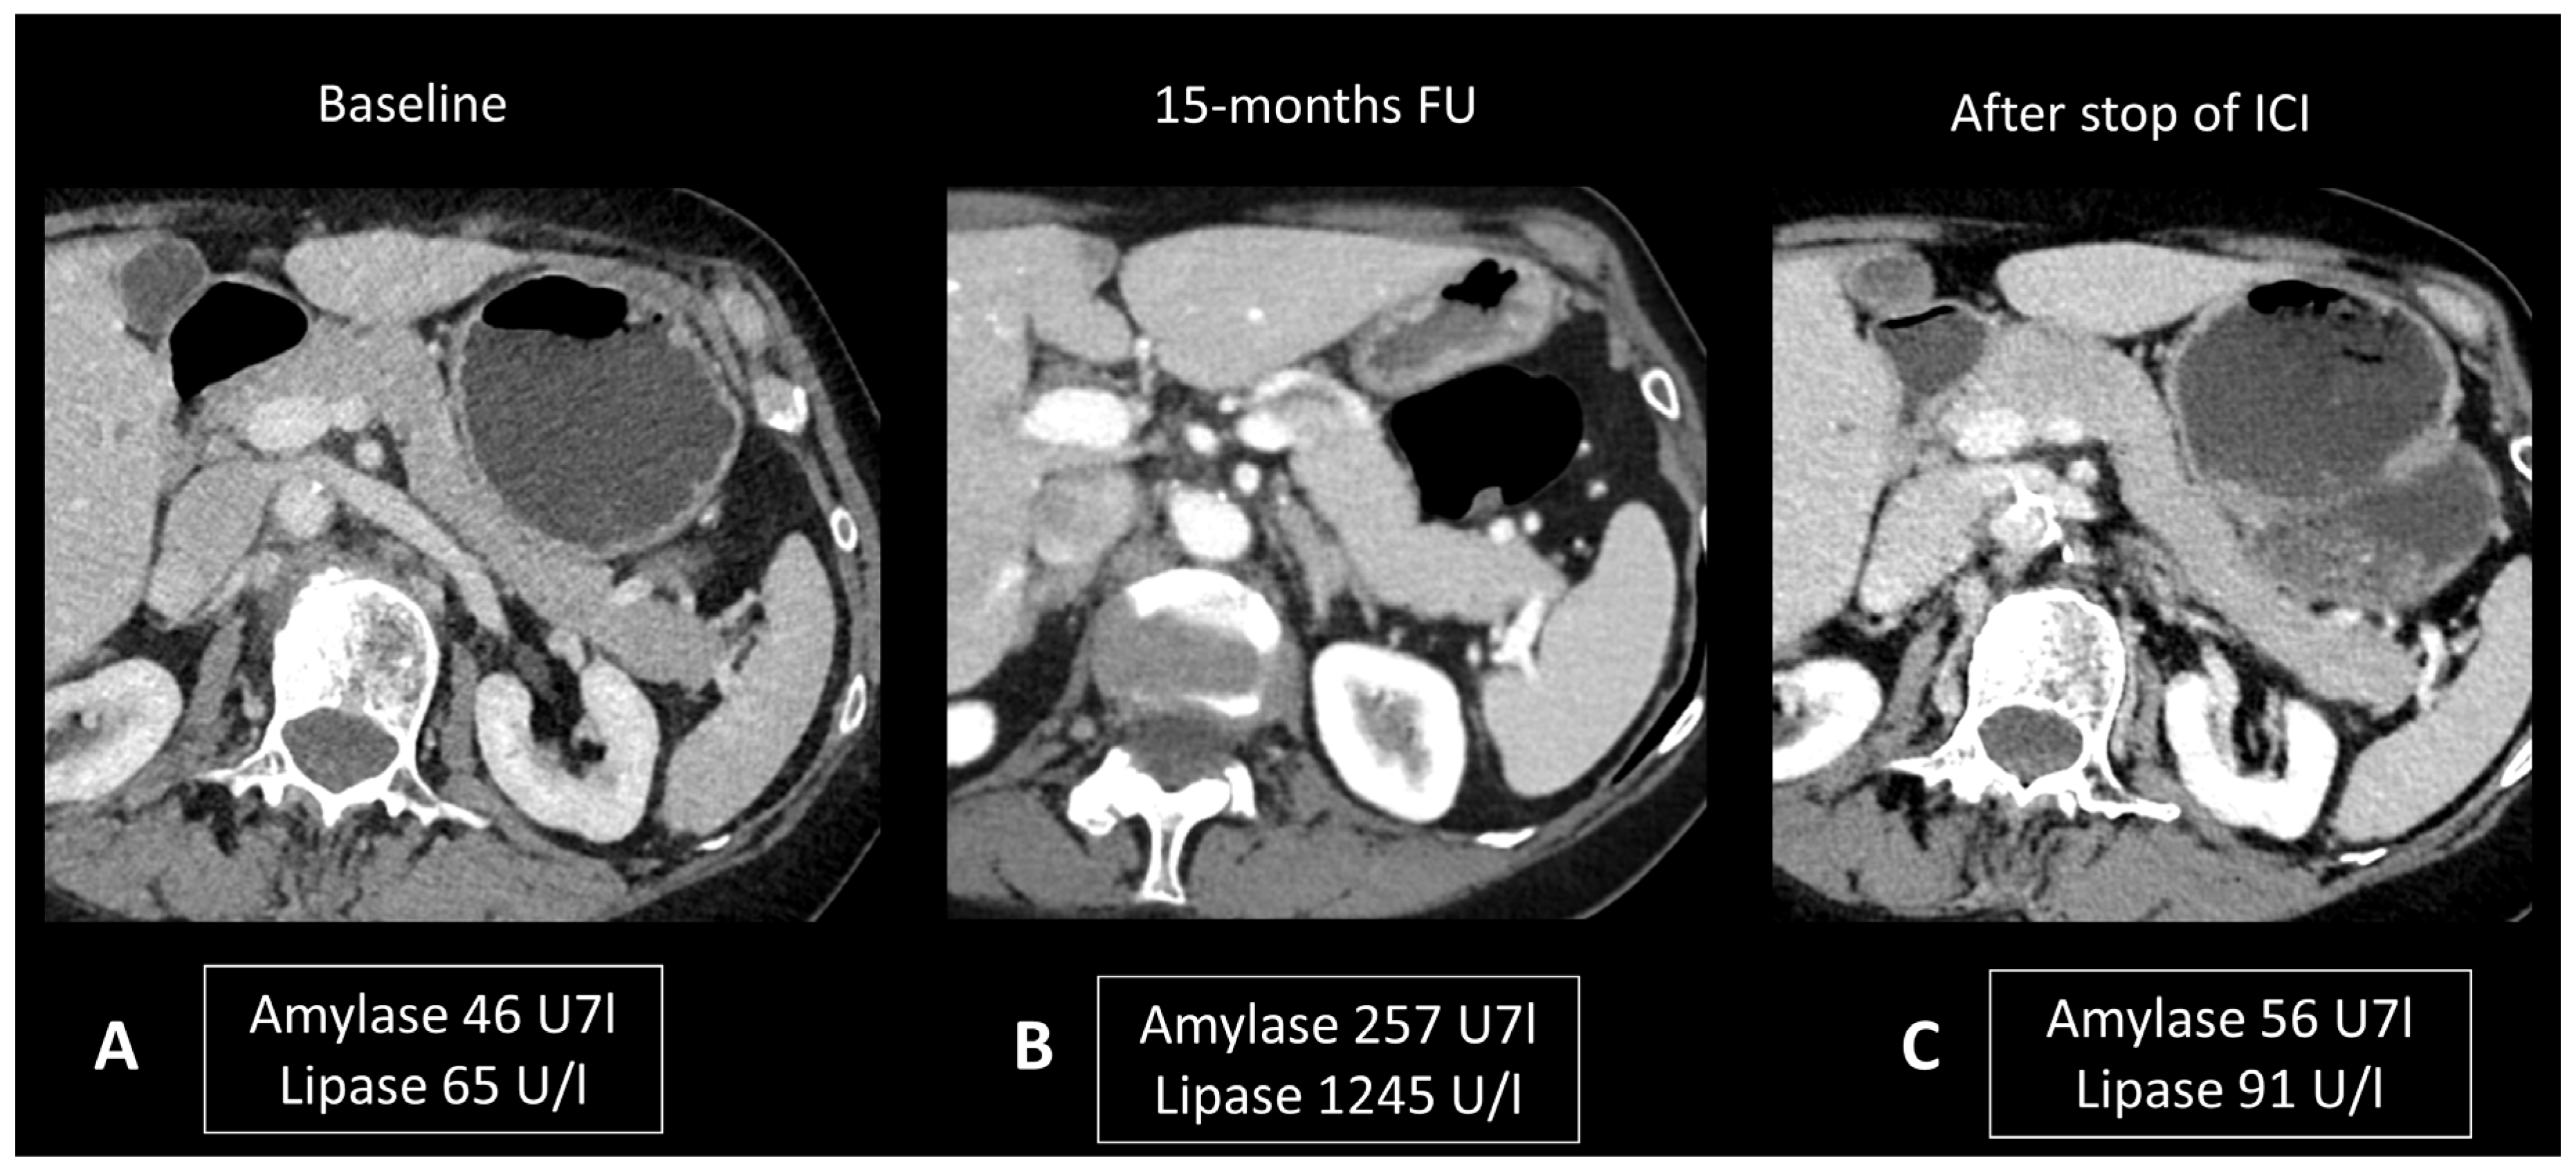

Ultrasonography (US) is useful to rule out bile stones. When examined through CT scans, ir-pancreatitis exhibits a pattern resembling pancreatitis from other origins, including focal or diffuse pancreatic enlargement, decreased enhancement, and peripancreatic fat stranding, or a mass-like enlargement such as in autoimmune pancreatitis (Figure 7) [24,83,84]. However, it’s important to note that these Ir-pancreatitis may also present with normal findings. CT or sometimes MRI is recommended as a one-stop-shop examination to assess pancreatitis severity and to rule out pancreatic metastases and other causes of pancreatitis. In particular, by adding cholangiography sequences, MRI can evaluate the presence of pancreas divisum or biliary stones. CT images are acquired at both the “pancreatic phase” and the “portal venous phase”, around 40 and 65 s after iodinated contrast agent injection. MRI protocol includes T2w and T2 Fat Sat for anatomic details and evaluation of necrosis and effusion, and T1w before and after gadolinium agent injection to assess hemorrhage and vascular supply. Post-contrast acquisitions are obtained at the “hepatic phase”, “portal venous phase”, and “interstitial phase”, around 35 s, 65 s, and 3 min after injection, respectively. Cholangiography sequences are three-dimensional heavily T2-weighted sequences that allow the depiction of the biliary and pancreatic ducts by enhancing their signal compared to the surrounding structures. Ir-pancreatitis manifests as increased uptake of 18F-FDG in the pancreas on PET/CT scans, with a correlation between the degree of uptake and the severity of pancreatitis [85].

Figure 7.

Immune-related pancreatitis in a patient with high-grade serous ovarian carcinoma treated by ipilimumab + nivolumab as the second line of treatment. Transverse CT images performed 15 months after initiation of treatment (B), due to elevated lipase and amylase levels, show a subtle diffuse enlargement of the pancreatic gland compared to the baseline CT scan (A). Note the regression of this enlargement after cessation of treatment and normalization of pancreatic enzymes (C).

As mentioned above, isolated asymptomatic hyperlipasemia should not prompt any treatment. For symptomatic patients, management includes a clear liquid diet (i.e., bowel rest, intravenous fluids) [10]. The benefits of glucocorticoid administration are not clearly demonstrated and data are limited to retrospective cases [83].